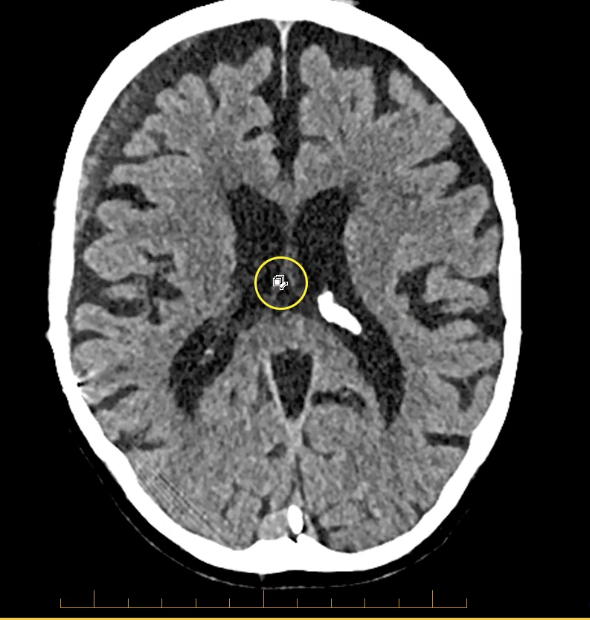

New cards

term image

structure down the midline of brain- falx cerebri

when assessing for midline shift of brain will form a tent superior to cerebellum

calcified choroid plxus in lateral ventricles